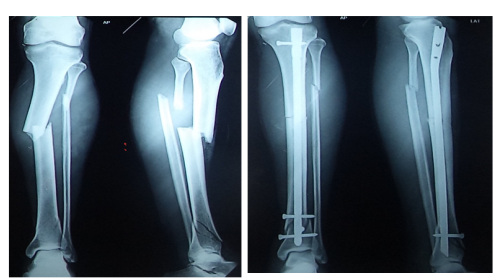

We have got 206 bones in our body. Each bone is strong and compact but they can withstand only a particular amount of weight and force. If the weight and force exceed the capacity of that particular bone then the bone will bend and get fractured. If the fractured fragments are very near to each other they unite very easily. This kind of fractures can be treated without surgery by the use of plaster of Paris. Like that the hairline fractures can be immobilised for a few weeks so that the fracture will unite on its own.

In modern orthopaedic management first, we take an x-ray of the fracture and analyse the type of fracture and according to the nature of injury, we treat the fracture.

We treat either with the help of a plaster of Paris bandage or we do surgery.

And in both the methods we do a check x-ray to confirm the position of the bones.